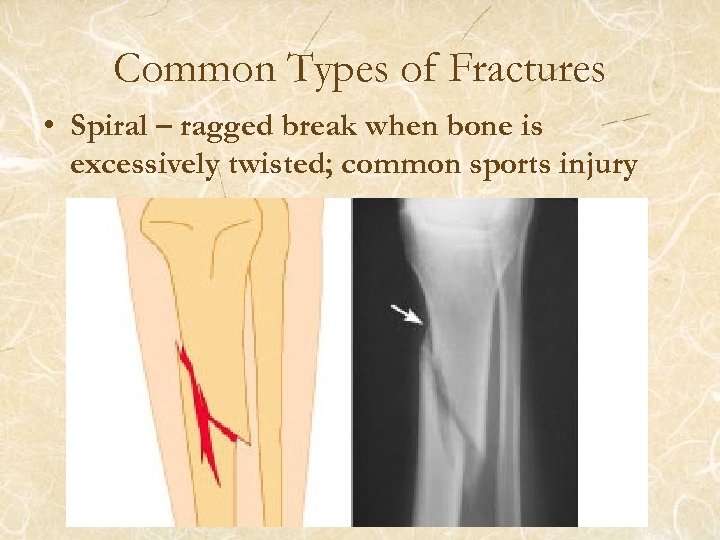

Common Types of Fractures • Spiral – ragged break when bone is excessively twisted; common sports injury